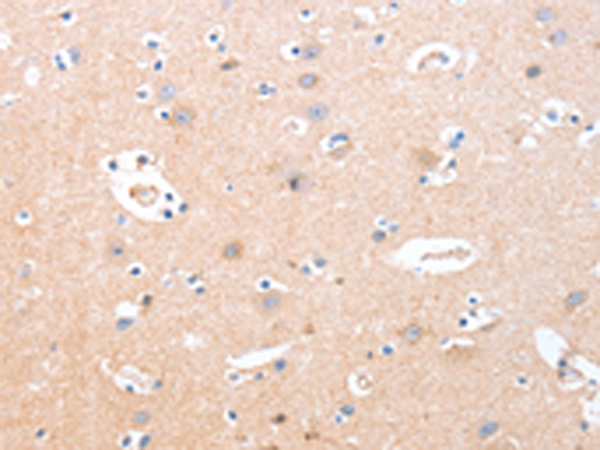

分类: 科研抗体货号: P04684别名: ANKYRIN-G应用: IHC反应种属: Human